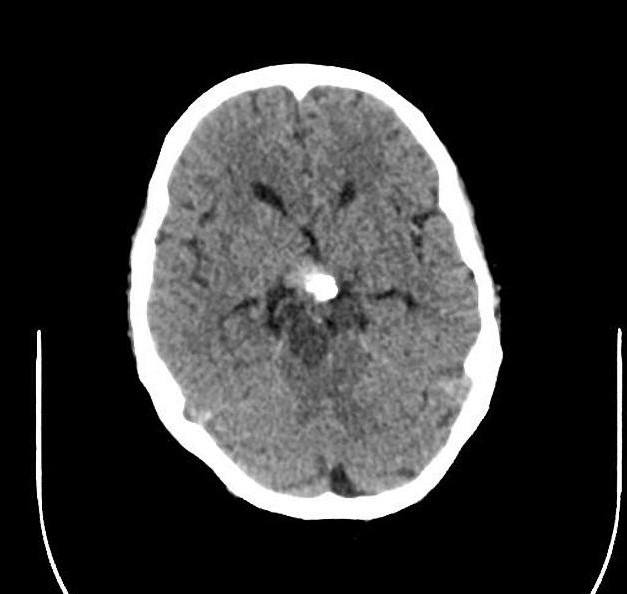

U sọ hầu

» Thông tin: Nam giới – 30 tuổi.

» Lâm sàng: Đau đầu.